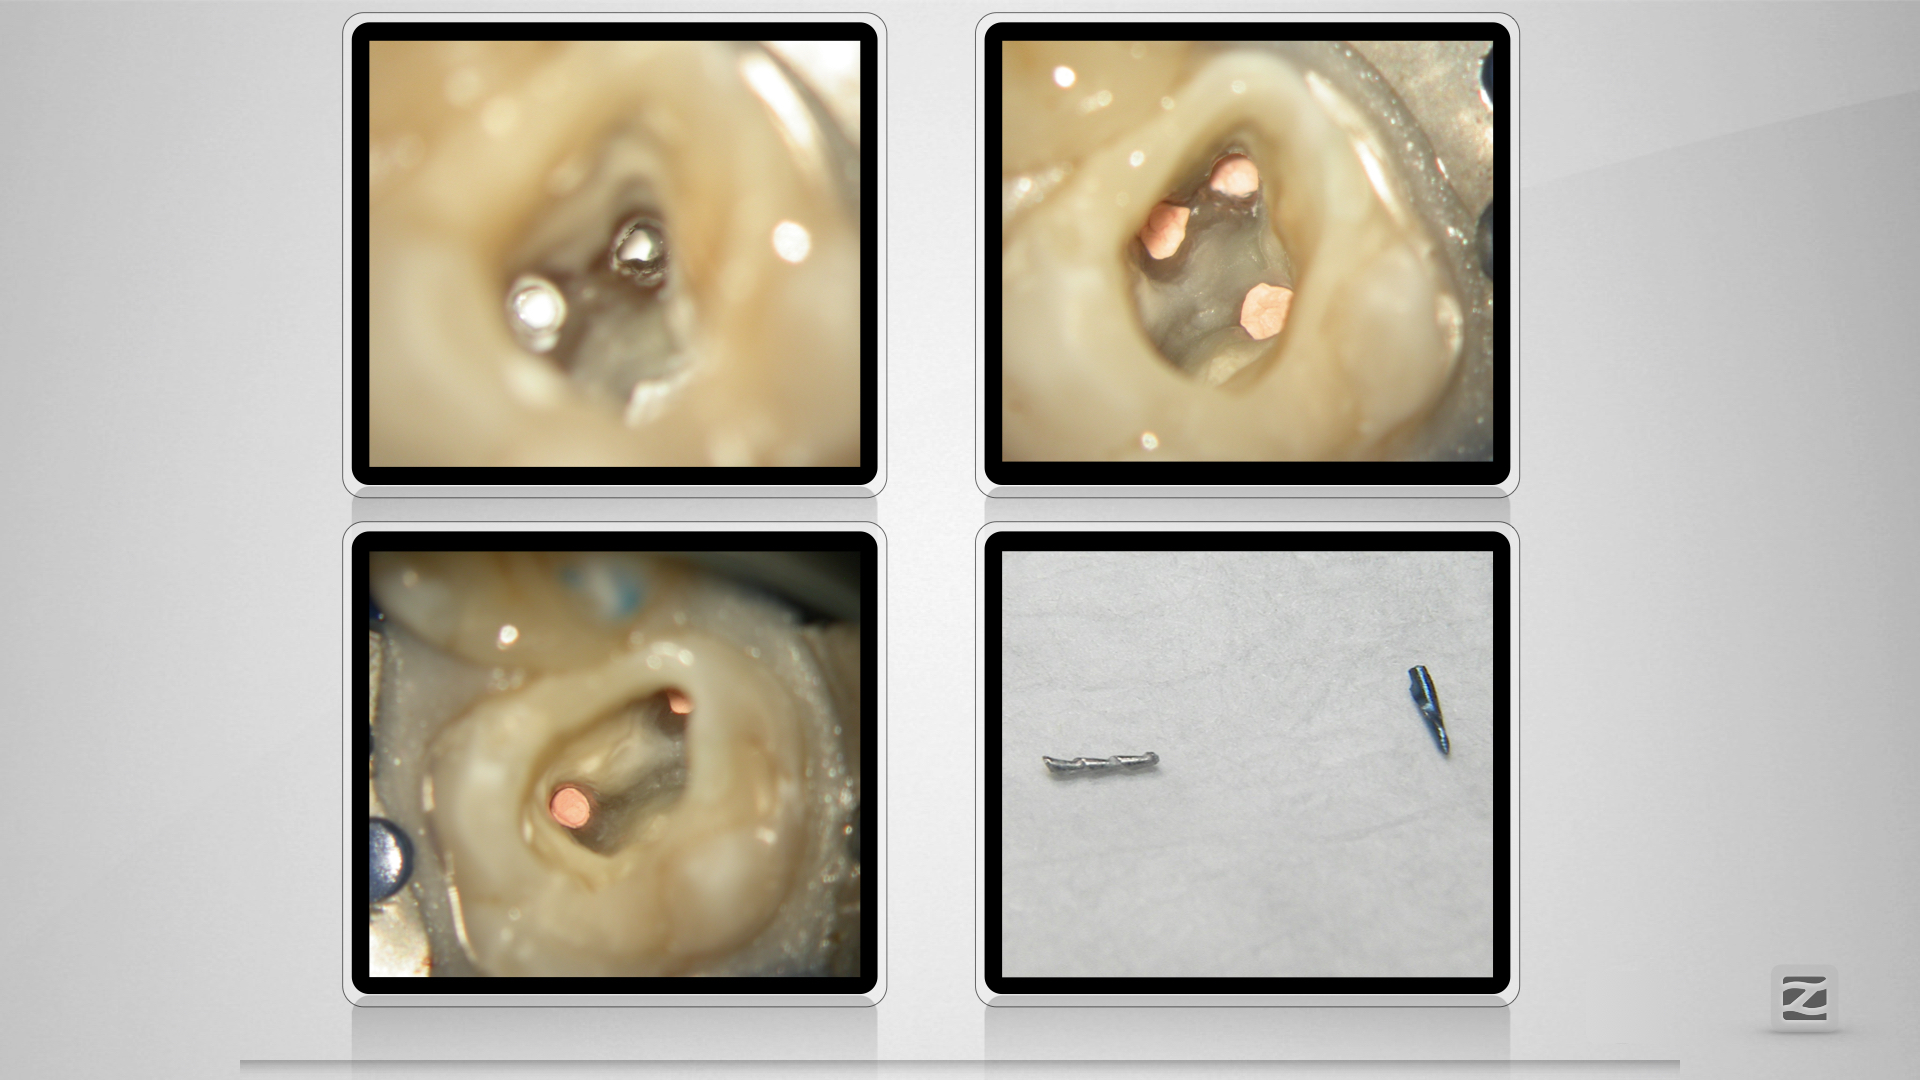

16D.007

Blue(s)